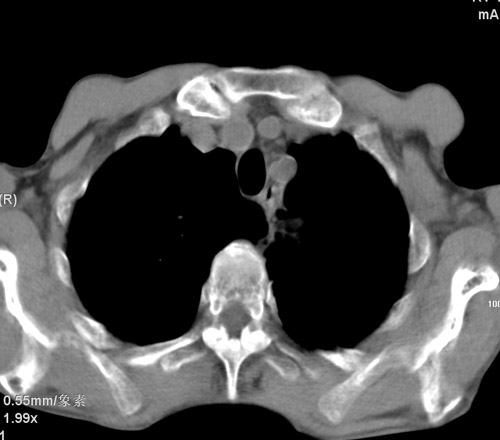

标题: CT17529:男 76 胸背部不适半月 胸透支气管炎 行CT检查 [打印本页]

标题: CT17529:男 76 胸背部不适半月 胸透支气管炎 行CT检查

意见 老年肺 少许炎症 肺大泡 右肺门略大 但支气管通畅  请各位高手指教如何下意见

间质纤维化伴少许炎症!另:肺大泡形成!

慢支肺气肿,肺动脉高压.